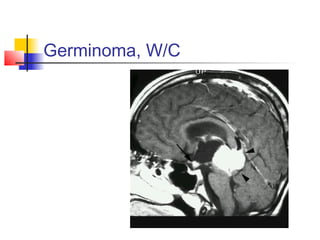

3. GERMINOMAS

 Pineal tumors, invade the adjacent

structures, and spread via CSF.

 Presents with the triad of visual loss,

decreased libido and DI.

 CT: iso- to hyperdense, ill defined,

uniform enhancement.

MRI: homogenous, hypointense in T1,

hyperintense in T2, marked

enhancement.

 Very sensitive to radiation.

2. GERMINOMAS

 This pineal tumor is always invading the

adjacent structures.

 More common in young males.

 In males it usually causes precocious

puberty;in both sexes it can be associated

with Parinaud’s syndrome and

hydrocephalus.

 Open biopsy is done, if reveals germinoma,

debulk and then radiate (local and total).

Germinoma, W/C